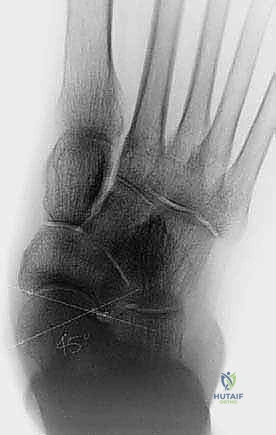

* الأشعة السينية أثناء الوقوف (Weight-bearing X-rays): وهي خطوة أساسية لتقييم زوايا العظام (زاوية ميري Meary's Angle، زاوية التغطية الكاحلية الزورقية Talonavicular Coverage Angle). تكشف هذه الأشعة عن مدى الهبوط والانحراف العظمي.